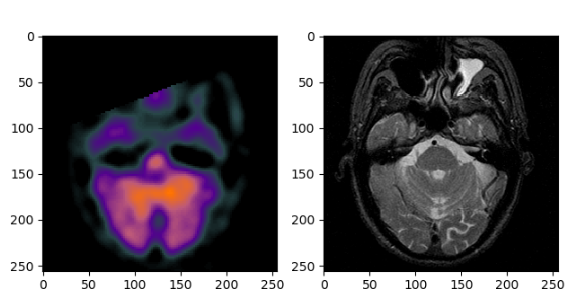

2 imageio

import imageio

spect = imageio.imread(file_name1)

mri = imageio.imread(file_name2)

print(spect.shape) # (256, 256, 3)

print(mri.shape) # (256, 256)

import matplotlib.pyplot as plt

fig=plt.figure()

f1 = fig.add_subplot(121)

f2 = fig.add_subplot(122)

f1.imshow(spect)

f2.imshow(mri,cmap='gray') # 注:单通道灰度图必须加上cmap='gray'才能正确显示

plt.show()